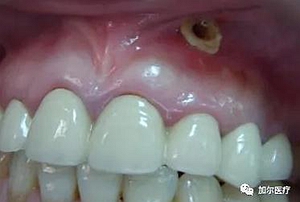

根管治療后長膿包怎么辦?

到這一步操作會更復(fù)雜,最好的方式就是先拍片檢查根尖部位,服用甲硝挫等藥片進行消炎,處理干凈瘺管周圍膿液,最后重新根管治療,要注意自己不能挑破,避免瘺管再次感染,另外單靠吃消炎藥只能治標(biāo)不治本,還是會反復(fù)起膿包,我們建議

得到正規(guī)醫(yī)院檢查治療根尖周炎,確保根管治療的成功率。